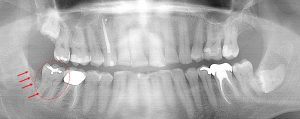

This 52 year old patient had the lower right 3rd molar extracted 6 years earlier due to a chronic infection. The boney defect (arrows) posterior to the 2nd molar (circled) is a site with a chronic gum infection present. Repeated cleaning is necessary to prevent further bone loss around the 2nd molar. Note the other two 3rd molars laying in the bone.